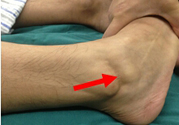

一般來說,膝蓋關(guān)節(jié)韌帶斷裂后,會多多少少的留些后遺癥的。只是看個人的恢復(fù)情況,會出現(xiàn)的后遺癥有,如:陰天、下雨、傷處酸痛等癥狀。建議在日常的飲食中要多食用些新鮮的蔬菜和水果,同時還要經(jīng)常的食用些如牛奶、豆制品之類的食物。

韌帶斷裂后,如果不能徹底治愈康復(fù),以后關(guān)節(jié)就會出現(xiàn)彎曲受限等不適現(xiàn)象,早期一般都會有僵硬拉扯感、關(guān)節(jié)彎曲活動受限制等癥狀。